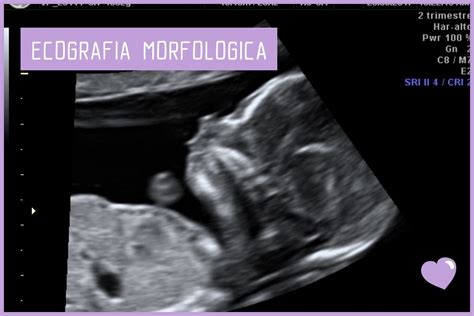

In questo periodo, sono tre i controlli che dovresti effettuare: l’emocromo, l’esame delle urine e, se non l’hai ancora effettuata, l’ecografia morfologica.

L'ecografia morfologica si effettua tra la 19a e la 22a settimana di gravidanza. È un appuntamento importante, ricco di attesa e di emozione, oltre che di comprensibili timori. Questa ecografia ha lo scopo di eseguire uno studio dettagliato dell'anatomia fetale. La morfologica servirà a controllare il corretto funzionamento di tutti gli organi (soprattutto cervello e cuore) e le loro dimensioni. Verrà anche controllata la perfetta chiusura del tubo neurale per scongiurare il pericolo di spina bifida. Se hai preso con regolarità l'acido folico il problema non dovrebbe sussistere. Molti medici consigliano di continuarlo per tutta la gravidanza e anche durante l'allattamento. Se hai fatto la morfologica, quasi sicuramente sai se aspetti un maschietto o una femminuccia.

L'ecografia servirà anche per monitorare altri aspetti importanti. Il cordone ombelicale è la struttura che permette il passaggio di sostanze nutrienti e ossigeno per il tuo bambino durante tutto lo stadio embrionale e fetale, collegato alla faccia fetale della placenta. Il Doppler analizza la circolazione fetale e uterina, in modo da fornirci informazioni relative alla crescita fetale. Come si calcola la lunghezza del feto? Di solito, dopo l'ecografia morfologica (che si effettua tra la 19a e la 22a settimana), la lunghezza del tuo bambino viene calcolata dalla testa al tallone. Fino alla 19a-20a settimana, invece, la lunghezza viene misurata dalla testa all'osso sacro-coccige: le sue gambe infatti non sono ancora ben formate e sarebbe quindi complicato valutare la lunghezza effettiva del corpo. Ma, visto che il bambino nel pancione assume in genere la posizione fetale e si muove molto, come è possibile misurarne la lunghezza dalla testa ai piedi? Il ginecologo che esegue l'ecografia si basa sulla lunghezza del femore, l'osso più lungo dello scheletro umano, che è circa un settimo della lunghezza totale. Il medico moltiplica quindi per 7 la lunghezza del femore e la combina il risultato con la misura di altri parametri, in modo da avere un quadro più preciso dell'età gestionale del feto.